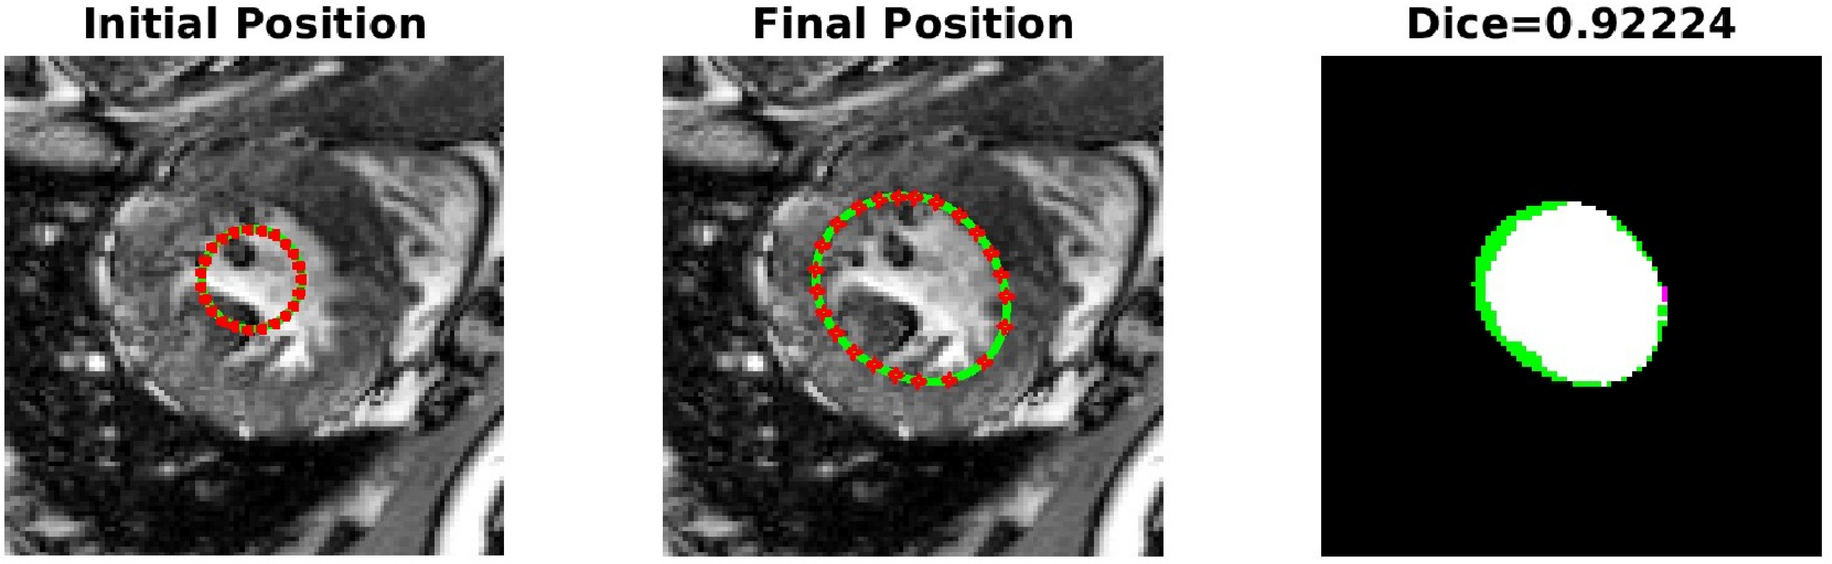

High Dice score: Effect of inclusion of convexity preserving shape prior in segmentation of the left ventricle.